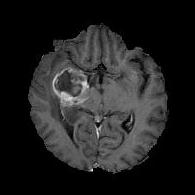

We first introduce a method for connecting the output of a CNN to an ACM, yielding a model for the precise delineation of lesions, to which we refer as Deep Active Lesion Segmentation (DALS) (Figure 4). We then go further to introduce a truly unified framework (Figure 5) that bridges the gap between ACMs and CNNs by leveraging a novel, automatically differentiable level-set ACM with trainable parameters that allows for back-propagation of gradients and can be end-to-end trained along with a backbone CNN from scratch, without any CNN pre-training. The ACM is initialized directly by the CNN and utilizes an energy functional that is locally-tunable by the backbone CNN, through 2D feature maps. Thus, our work overcomes the big hurdle of fully automating the powerful ACM approach to image segmentation. We have applied our proposed framework to the task of building segmentation in aerial images (Figure 6).

Deep Active Lesion Segmentation

[45]: Lesion segmentation is an important problem in computer-assisted diagnosis that remains challenging due to the prevalence of low contrast, irregular boundaries that are unamenable to shape priors. We introduce Deep Active Lesion Segmentation (DALS), a fully automated segmentation framework that leverages the powerful nonlinear feature extraction abilities of FCNs and the precise boundary delineation abilities of ACMs. Our DALS framework benefits from an improved level-set ACM formulation with a per-pixel-parameterized energy functional and a novel multiscale encoder-decoder CNN that learns an initialization probability map along with parameter maps for the ACM. We evaluate our lesion segmentation model on a new Multiorgan Lesion Segmentation (MLS) dataset that contains images of various organs, including brain, liver, and lung, across different imaging modalities—MR and CT. Our results demonstrate favorable performance compared to competing methods, especially for small training datasets. -